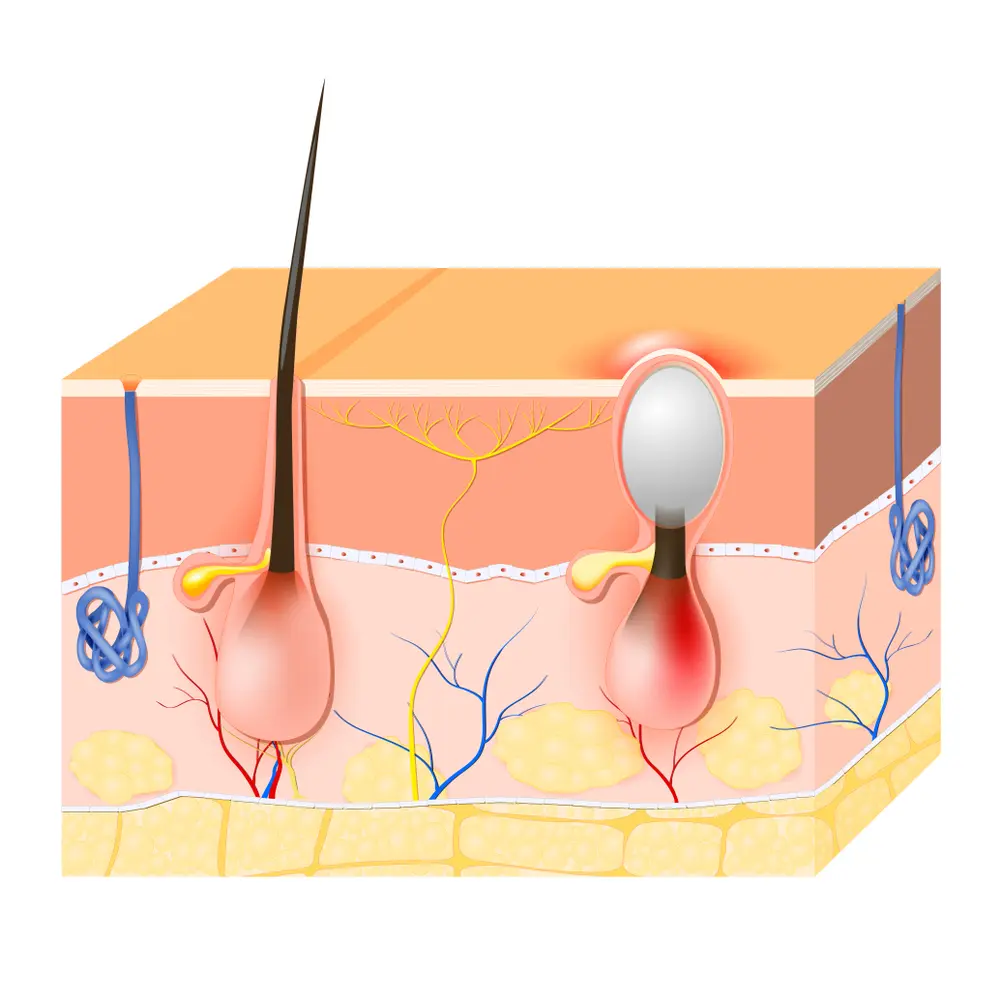

Acne is caused by a combination of factors, including overactive sebaceous glands, bacteria, and the buildup of dead skin cells.

Naturopathic care such as dietary modifications and topical applications of natural oils and herbs have been found to be very effective at addressing acne in many cases. The skin is the largest organ of the body. It contains more than 100,000 sweat and oil glands that produce an oily substance called sebum. This happens so that the skin can be water-proof and prevent moisture loss.